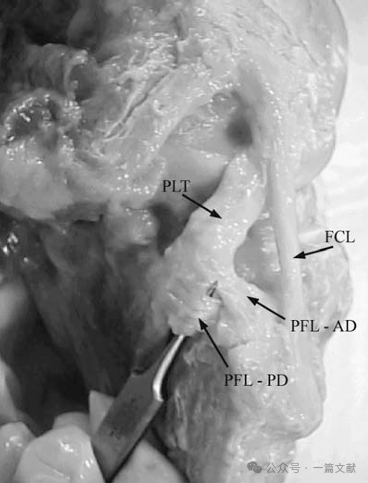

2.膝关节腘肌复合体:除腓侧副韧带外,腘肌复合体构成膝关节后外侧另一重要的静态稳定结构。该复合体彼此形成复杂的相互作用:包括腘肌腱股骨附着部、三组腘肌半月板束(前下束、后上束与后下束)、分前后两束的腘腓韧带、后关节囊及外侧半月板后角的腱膜附着部,以及腘肌肌腹本身。腘肌腱股骨附着部始终位于腓侧副韧带股骨附着点的前方。

腘肌腱股骨附着部:

腘肌腱(PLT)与腓侧副韧带股骨附着点间距为18.5毫米:

腘腓韧带(PFL)的后束(PD)与前束(AD)。(进化历程来看,腓骨头曾与股骨构成关节,后逐渐向远端迁移至现有位置——即与胫骨后外侧关节面相接[1-4]。当腓骨仍与股骨相连时,腘肌起自腓骨;随着高等动物中腓骨远端迁移的发生,腘肌腱逐渐获得股骨附着点,这很可能是腓股半月板残迹发育并融入腘肌腱的结果[1-6]。此外,近端腓骨向远端迁移时,似乎牵拉外侧关节囊同步下移,从而形成了腘肌裂孔[5]。值得注意的是,尽管腘肌复合体在进化过程中获得了股骨外侧的附着点,但仍保留了其与腓骨的连接(即腘腓韧带))